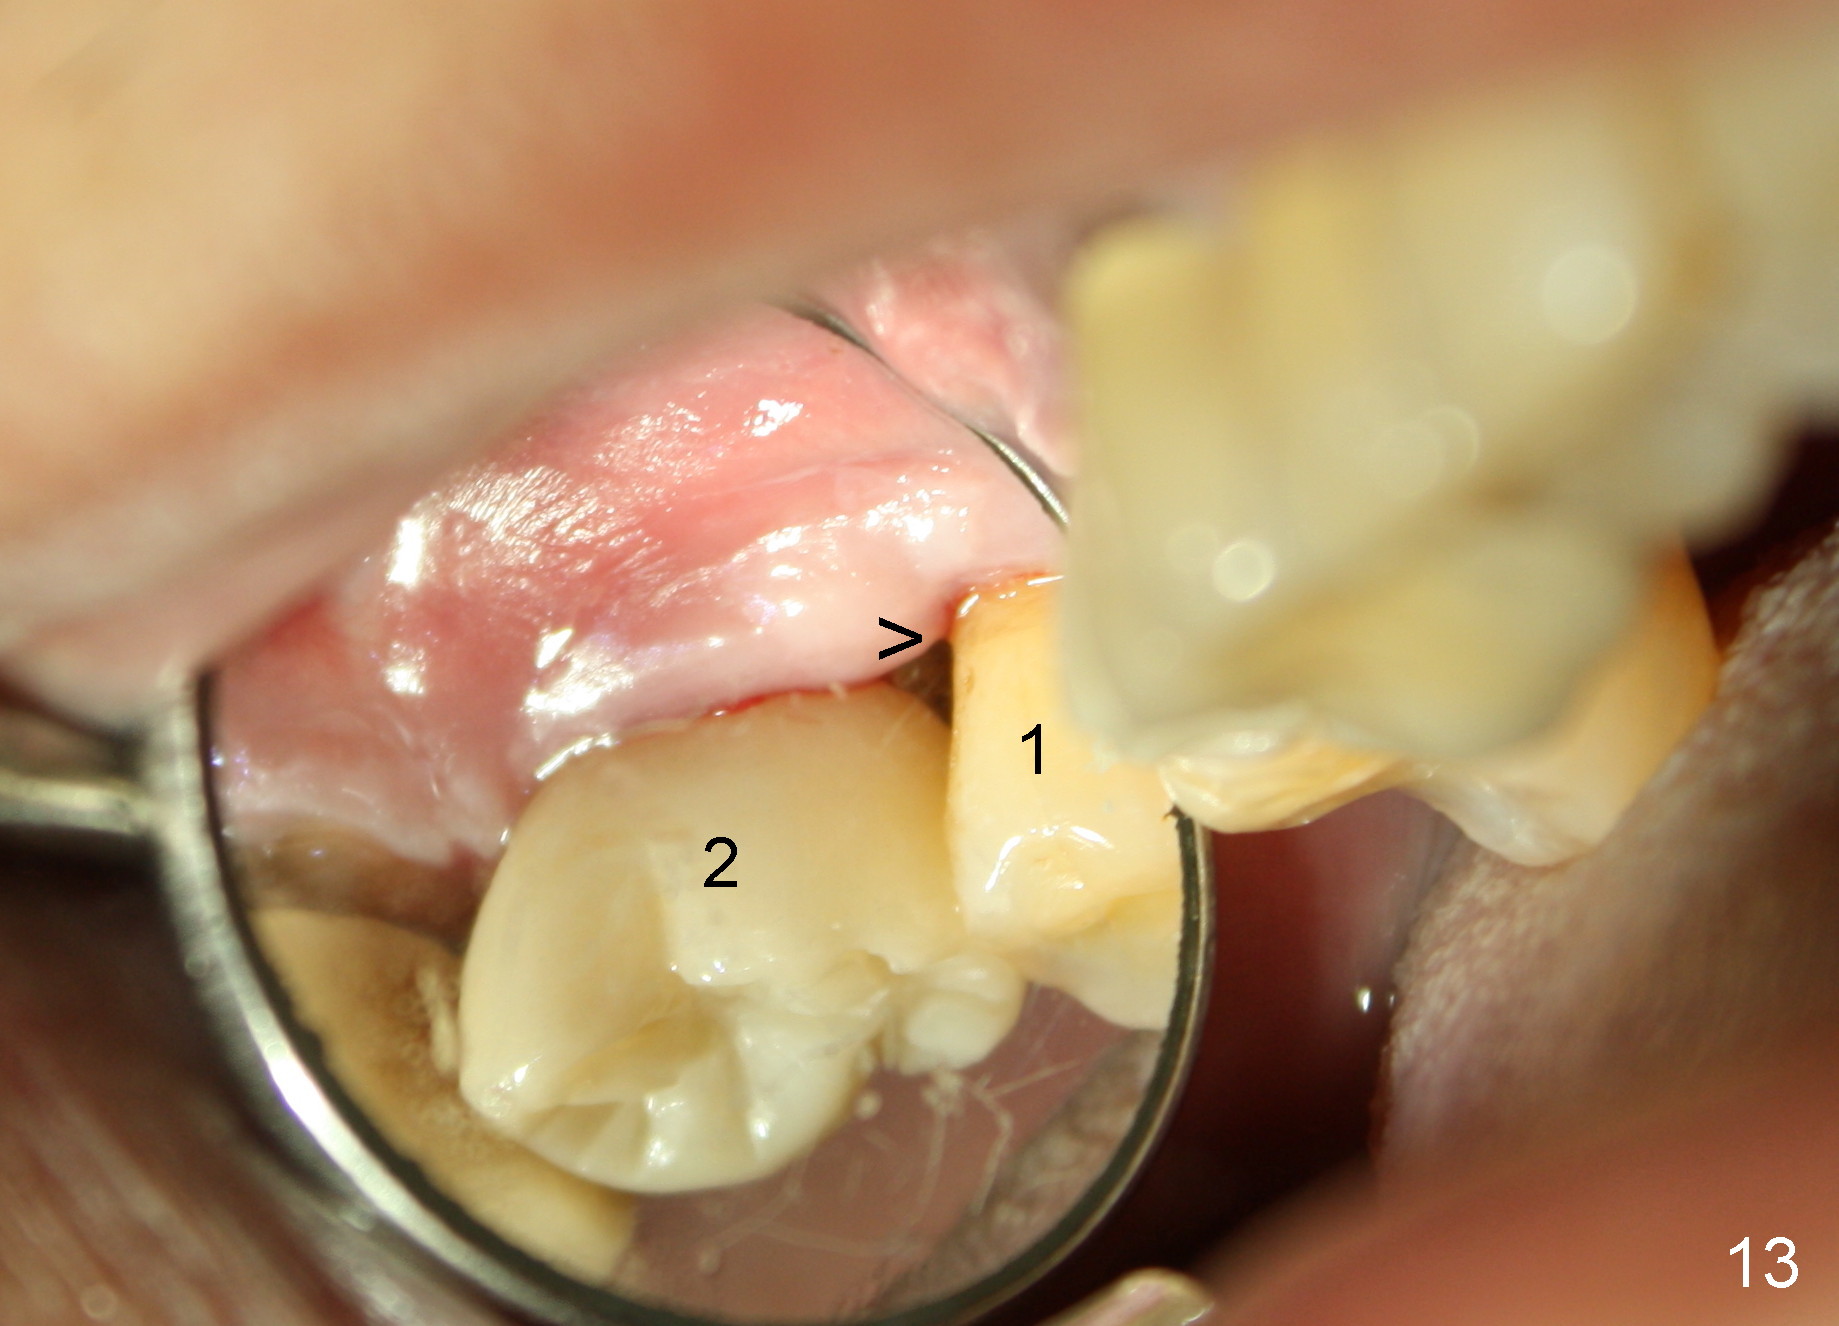

The patient complains food impaction between #1 and 2, six months post cementation. The former has mobility II. Although there is keratinized gingiva buccal to these sites (Fig.12), there is no papilla buccally (Fig.13) or palatally (Fig.14). The palatal pockets between #1 and 2 are deep with tenderness. X-ray shows bone loss between the sites (Fig.11 white *); the periodontal explorer can be felt to touch the distal implant threads (<). Extraction and immediate implant are recommended for #1. Twelve months later, the patient agrees with the treatment plan. The tooth #3 needs extraction and immediate implant, 2.5 years after the one at #2.